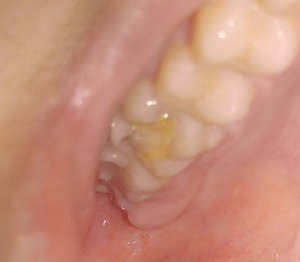

4 месяца назад мне сделали вкладку на предпоследний зуб нижней челюсти, при этом рядом стоящий ближний зуб удалили, т.к. было нагноение на десне. Я не сделала коронку на один зуб, т.к. хотела закрыть просвет и от недостающего зуба. Но и стачивать ближний зуб (здоровый) мне не хотелось. На дорогой имплант средств не нашлось. Сейчас зуб со вкладкой стал побаливать и на десне снова появилось нагноение. Из-за чего это произошло и что мне теперь делать? Явилось ли моё промедление результатом нагноения или это могло произойти и под коронкой?

Добрый день . Конечно это произошло бы и под коронкой, так что не мучайте себя. Дело в самих каналах, вернее в плохо пролеченных каналах, что повлекло обострение воспалительного процесса.

Одним словом вам необходимо к врачу и как можно раньше и постараться спасти зуб.